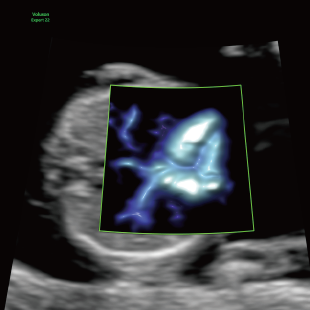

妊娠中期になると、胎児の体や内臓の構造がよりはっきりと確認できるようになります。 中期スクリーニングでは、頭部、顔面、頸部、胸部、腹部、心臓、手足、外性器、臍帯や胎盤など、全身をくまなく観察し、形態の状態を詳しく確認します。この頃に染色体数の変化を疑わせる所見が確認される事もあります。

胎児ドックの様子_中期_頭 胎児ドックの様子_中期_顔面 胎児ドックの様子_中期_心臓 胎児ドックの様子_中期_腹部 胎児ドックの様子_中期_足 胎児ドックの様子_中期_4D

妊娠後期は、胎児の成長がさらに進み、発育の途中で現れてくる変化を確認できる時期です。中期の検査では問題が見られなかった場合でも、成長に伴って形態の変化が現れることがあります。また、構造だけではなく、胎児機能(赤ちゃんの元気度)の評価も可能となります。後期スクリーニングでは、各臓器の状態や構造に加え心臓の動きや血液の流れなどをより詳しく観察します。

胎児ドックの様子_後期_頭 胎児ドックの様子_後期_心臓 胎児ドックの様子_後期_心臓 胎児ドックの様子_後期_足 胎児ドックの様子_後期_4D